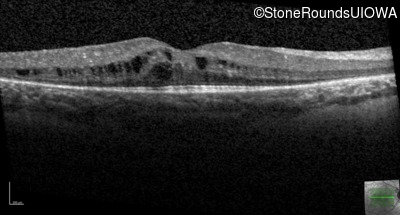

Age at visit: 7 years

OD OS

Age at visit: 7 years (Visit 2)